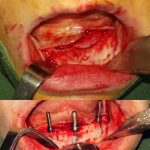

• انجام بی حسی و برداشتن تاج دندان

بعد از اینکه معاینات اولیه انجام شد، با انجام بی حسی موضوعی در فک شما، دندانپزشک اقدام به برداشتن قسمت کمی از تاج دندان می کند و سطح پوسیده به طور کامل برداشته می شود.